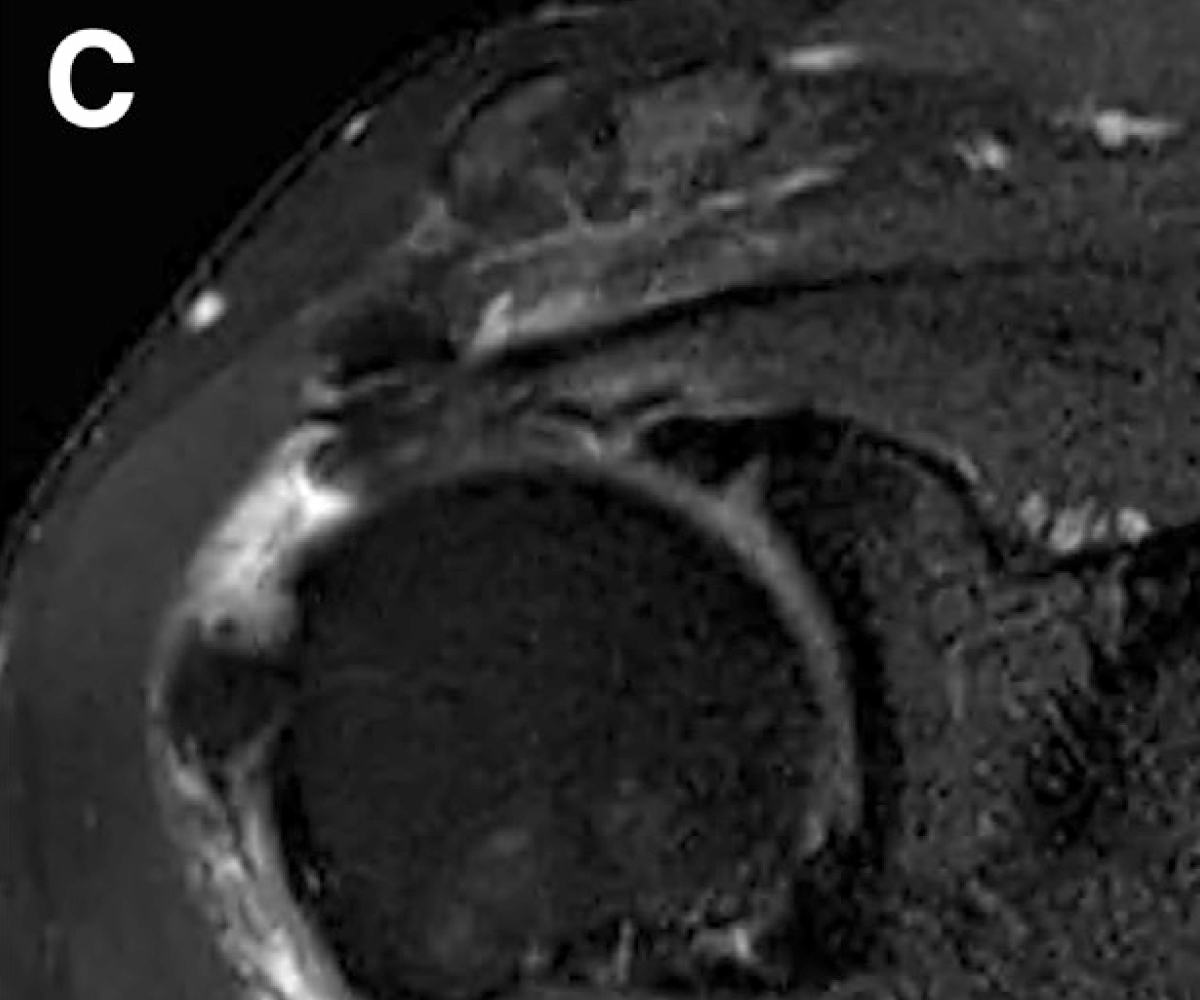

회전근개는 손상이 진행되면 부분파열이 되어 광범위 파열로 커질 수 있고,

옷감이 낡아 해지듯 힘줄도 점점 닳아 끊어지는 양상을 보입니다.

리제네텐은 파열된 회전근개 부위에 콜라겐 패치를 덧대어

새로운 힘줄 조직 성장을 지원하고,

약 6개월 이내 점진적으로 흡수되며 새로운 조직층으로 바뀌는 방식입니다.